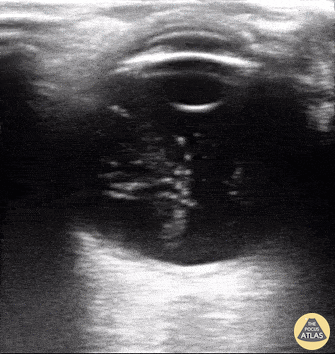

Orbital - Asteroid hyalosis (an ultrasonographic mimic of vitreous hemorrhage)

An 59-year-old male with PMH of ESRD presented with 10-day hx floaters in his right eye. Sonographic findings are shown, notable for multiple, mobile, hyperechoic densities that swirled rapidly with eye movement. The appearance is similar to that of vitreous hemorrhage. The patient was subsequently evaluated by ophthalmology who confirmed a diagnosis of asteroid hyalosis; a rare, benign condition of calcium phospholipid deposition within the vitreous fluid. The sonographic findings are so similar to vitreous hemorrhage that the two are commonly mistaken for each other. The clinical differentiation is that asteroid hyalosis is most often asymptomatic, and almost always without visual deficits (possibly benign floaters). These patients also rarely require vitrectomy. In addition to clinical presentation, asteroid hyalosis can be differentiated from vitreous hemorrhage by subtle sonographic features. In asteroid hyalosis, the hyperechoic calcium phospholipid particles have a sparkling, "starry sky" appearance compared to the typically duller heterogenous blood seen in vitreous hemorrhage. Vicky Lam, MD, MS; Christianna Sim, MD; Olusola Sanusi, MD Kings County Hospital, SUNY Downstate Emergency Medicine